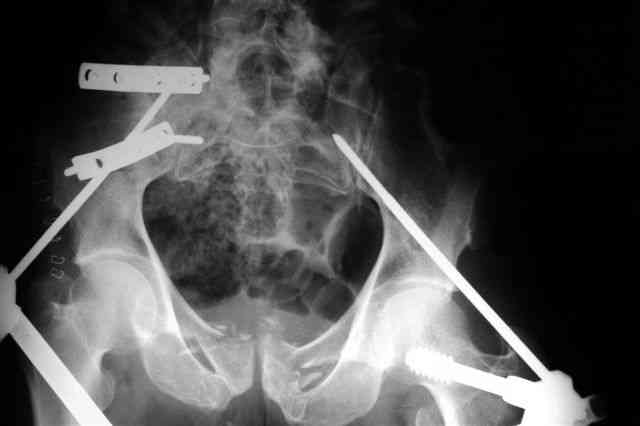

Вчера прооперировал больного.

Попытка низвести половину таза на тракционном столе ( скелетное вытяжение за бедро) безуспешная.

из переднего доступа добрался до правого КП сочленения , все запаяно костью, с помощью 2 шанцев винтов в крестец и подвздошную кость и элеватора репозиция, контроль ЭОП

и двумя пластинами фиксация.

Спереди, аппарат как рекомендовал Джолдас.

Снимки плохого качества( очень темные) завтра переделают и пришлю на конференцию.

На мой взгляд, смещение устранено и фиксация выглядит вполне анатомичной.

В приложении послеоперационные картинки.